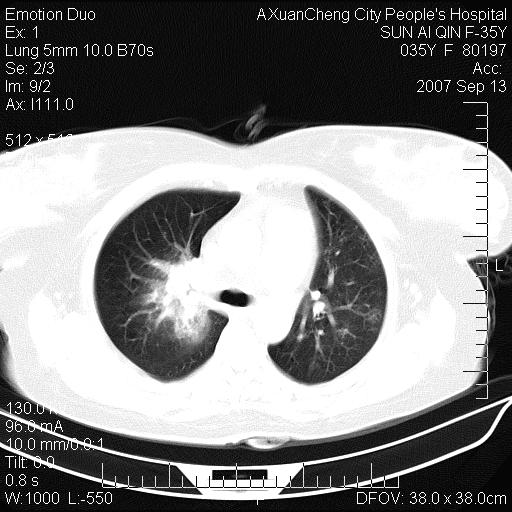

以下是引用天南地北在2007-9-13 13:43:00的发言:[br]考虑双肺、肺门侵润

以下是引用ydx_74在2007-9-13 15:42:00的发言:[br]仅看片,考虑右上肺癌并双肺转移,结合病史,考虑肺门、肺内淋巴侵润

以下是引用同在2007-9-13 15:08:00的发言:[br]支持肺门及双肺侵润.